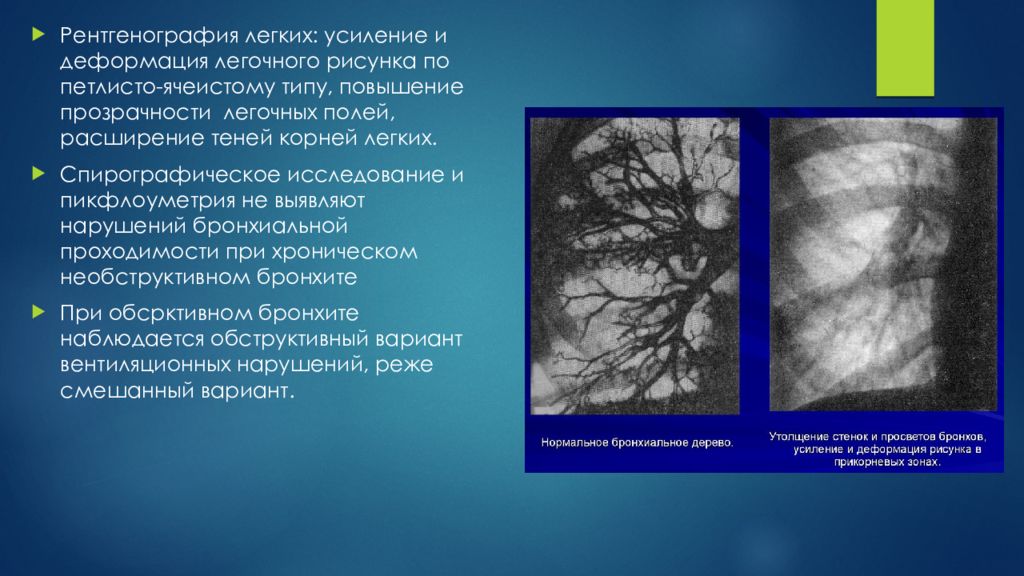

Фотографии, демонстрирующие обнаруженное усиление легочного рисунка

Раздел: Фотодневник открытий